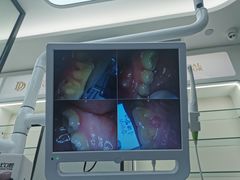

• 牙博士口腔(杨浦店)

• -牙博士口腔(杨浦店)